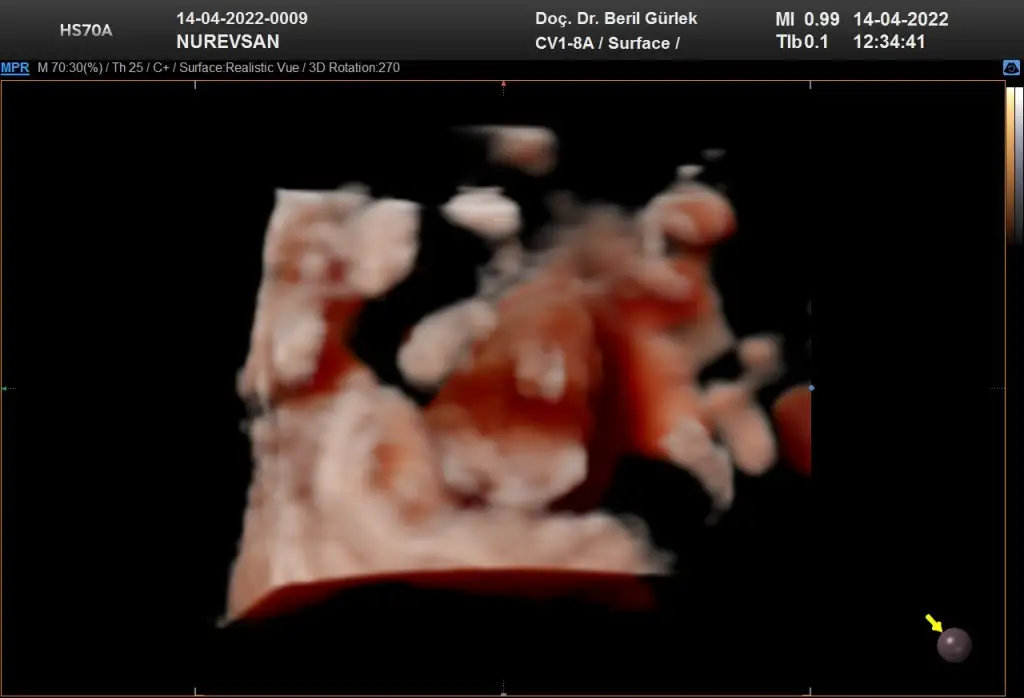

Ay ne güzel başlık banada tahmın edebılır mısın😊🤗 burda 8 haftalık karından bakıldı sımdı 10 haftalıgım 2 hafta sonra gidicem doktora bır tahmınde bulınabılır mısın

Burada 8 haftalık karından canım